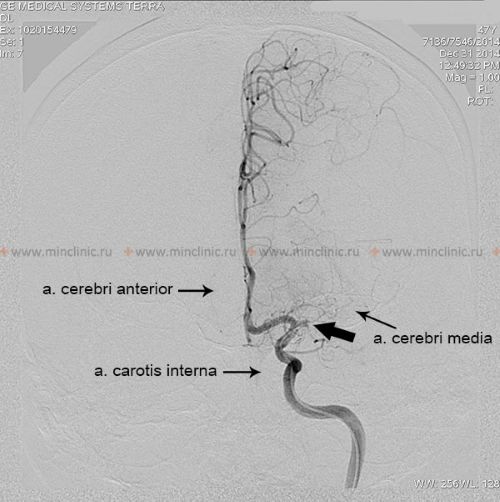

თუ ეჭვია ცერებრული არტერიის ემბოლიაზე, არტერიული ოკლუზიის ადგილმდებარეობის იდენტიფიცირება და ქვემოთმდებარე ტვინის ქსოვილის შეფასება კრიტიკულია მწვავე მკურნალობის (როგორიცაა თრომბექტომია) დასაგეგმად [16, 19]. არაინვაზიური სისხლძარღვოვანი ვიზუალიზაცია, როგორიცაა კტ ანგიოგრაფია (CTA) ან მრ ანგიოგრაფია (MRA), ჩვეულებრივ ტარდება გადაუდებლად [16]. კონვენციური კათეტერზე დაფუძნებული ცერებრული ანგიოგრაფია (ციფრული სუბტრაქციული ანგიოგრაფია - DSA) უზრუნველყოფს სისხლძარღვების უმაღლესი რეზოლუციის დეტალებს, მაგრამ არის ინვაზიური [14]. ის შეიძლება ჩატარდეს, თუ იგეგმება ენდოვასკულური მკურნალობა (თრომბექტომია) ან თუ არაინვაზიური ვიზუალიზაცია არასაკმარისად ინფორმატიულია [16, 19]. მნიშვნელოვანია აღინიშნოს, რომ რამდენიმე საათის ან დღის შემდეგ, ემბოლმა შეიძლება მიგრირება განიცადოს დისტალურად, ფრაგმენტაცია ან სპონტანური ლიზისი (დაშლა), რაც ნიშნავს, რომ მოგვიანებით ჩატარებულმა ანგიოგრაფიამ შეიძლება არ აჩვენოს თავდაპირველი ოკლუზია, რის გამოც ემბოლიური ინსულტის საბოლოო დიაგნოზი ზოგჯერ სავარაუდოა კლინიკური სურათისა და ინფარქტის პატერნის საფუძველზე [1]. სტანდარტული ინტრავენური კონტრასტის შეყვანა რუტინული კტ ან მრტ სკანირების დროს ზოგადად მოკლებულია იმ რეზოლუციას და დროით სიზუსტეს, რაც აუცილებელია სისხლძარღვებში მცირე ცერებრული ემბოლების უშუალო ვიზუალიზაციისთვის [14].